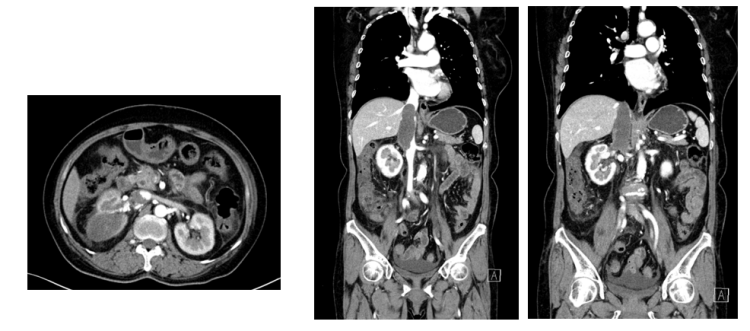

2023年6月14日泌尿系CTU增强:右肾及下腔静脉内富血供肿块,右肾癌并腔静脉癌栓达膈肌以上,肾占位最大横截面9.9cm×6.1cm,腔静脉占位最大横截面6.1cm,上下范围12.4cm,可见肝静脉栓子。

图1 泌尿系CTU增强(箭头所指为肝静脉癌栓)